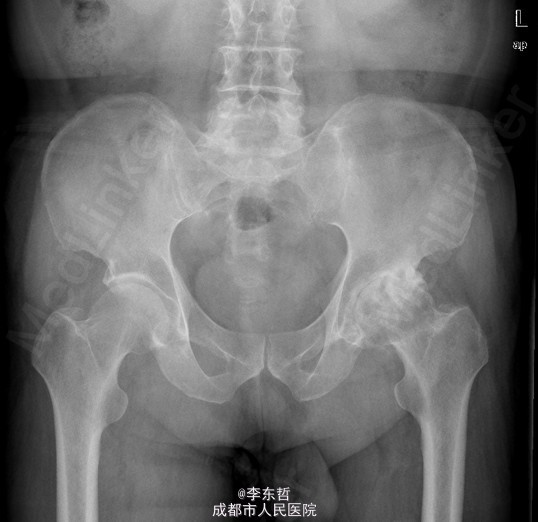

患者男,76岁,因“外伤致左髋部疼痛40多年,加重伴跛行2年”入院;患者自诉40多年前因一次摔伤致左髋关节脱位,给予手法复位后治愈,以后时有疼痛,关节活动好,不影响行走,4年前出现左髋部疼痛加重,活动后明显,休息后缓解,无腰腿痛,无肢体麻木等不适,给予对症治疗,稍有好转,以后反复发作,长时间行走后疼痛明显加重,2年前出现左下肢无力,长距离行走后出现跛行,且左髋关节有异响感;2月前出现左髋部疼痛加重,行走时尤为明显,步行约500米即出现疼痛,伴跛行,偶有静息痛;以后反复出现左髋部疼痛,并逐渐加重,严重影响日常生活;1月前于当地医院摄片提示左股骨头坏死,为求进一步治疗,遂来我院,门诊以“左髋骨关节炎”收入住院。 患者自患病以来精神、饮食、睡眠可,二便正常,体重无明显变化。

查体:左侧腹股沟中点深压痛,左髋部伴有轴向叩击痛,双下肢感觉正常,双足背动脉搏动良好。左下肢较右下肢短缩约2cm;左髋屈65°,伸0°,内收10°,外展20°,内旋5°,外旋10°,左髋活动受限,内外旋诱发疼痛;Thommas征阴性,“4”字试验阳性;左下肢肌力正常,活动良好,右侧正常 ;辅助检查:X片示:左侧股骨头塌陷、密度增高,股骨头坏死可能,左髋骨质疏松.。